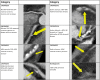

Methods: From the Copenhagen Comorbidity in HIV Infection (COCOMO) study, we included virologically suppressed PWH who underwent coronary computed tomographic (CT) angiography. Any atherosclerosis was defined as >0% stenosis, and obstructive CAD as ≥50% stenosis.